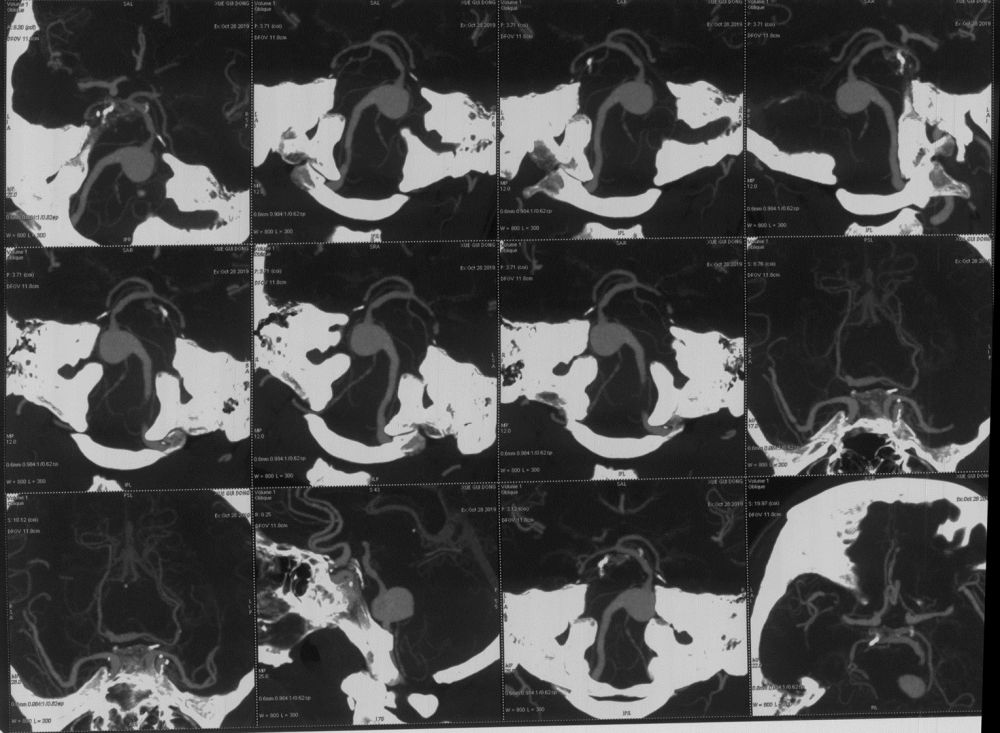

头颅CTA:基底动脉巨大动脉瘤。

图2 头颅CTA